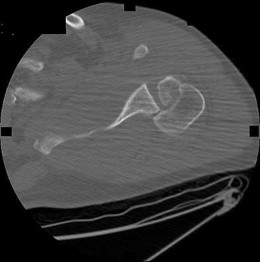

A 45-year-old manual laborer complains of chronic radial-sided wrist pain. He recalls a severe 'sprain' 10 years ago. Radiographs demonstrate scapholunate dissociation with advanced radioscaphoid arthritis. MRI confirms the radiolunate joint is spared, but the proximal capitate shows severe, full-thickness chondral wear.

Which of the following procedures is most appropriate to provide durable pain relief while preserving motion?

Explanation

The patient has Scapholunate Advanced Collapse (SLAC) pattern of the wrist. Stage III SLAC involves the capitolunate joint, while the radiolunate joint characteristically remains spared. Because the capitate head is severely arthritic, Proximal Row Carpectomy (PRC) is contraindicated, as it relies on a healthy cartilage interface between the capitate and the lunate fossa. Scaphoid excision with four-corner fusion (capitate, hamate, lunate, triquetrum) is the procedure of choice.